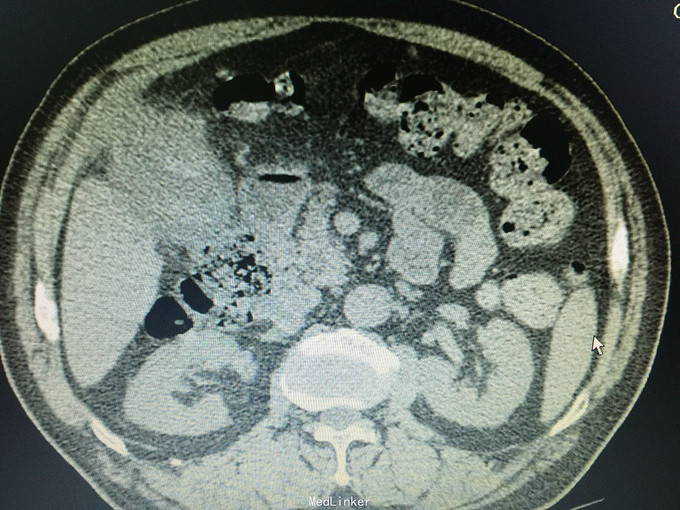

男,74岁 主诉:反复右上腹疼痛10年,再发并加重一天, 现病史:10年前开始反复右上腹疼痛,持续性绞痛,向同侧肩背部放散,曾经在当地医院以“胆囊结石”治疗,效果不佳,10年来反复发作,10小时前再次发作并疼痛难忍,来诊,无发热,无恶心、呕吐,尿色深,大便正常。

痛苦表情,皮肤及巩膜轻度黄染,腹部平坦,右上腹压痛,无肌紧张及反跳痛,未及包块,莫氏症阳性,肝区扣痛明显。 辅助检查:CT:胆囊轮廓欠清晰,密度不均,底部局限性增厚并向内突起,胆囊内见高密度影,胆总管扩张。

诊断:胆囊占位,胆囊结石,胆囊炎 处理:手术治疗,术中见大网膜与腹膜广泛粘连,胆囊质硬,与肝脏、12指肠及横结肠广泛粘连,与胃小弯及幽门部侵润致密。行胆囊癌根治术,胃破裂修补术,胆总管切开T形管引流,腹腔冲洗引流术。病理证实为胆囊中分化腺癌侵及浆膜层。(胆囊及胆总管内未见结石)